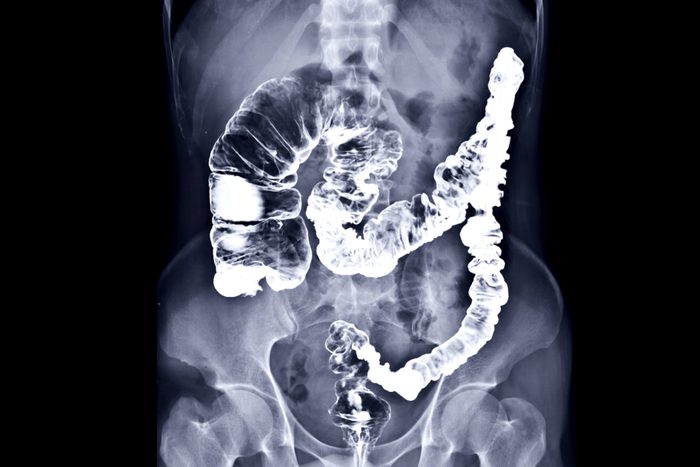

Colon cancer is striking adults at increasingly younger ages. These foods, drugs, and lifestyle habits can protect against colon cancer.

Did you know that, according to the American Cancer Society, colorectal cancer is the second leading cause of cancer-related deaths in men and women combined? While many people are very aware of the top killer—lung cancer—and other common cancers like melanoma and breast cancer, a concerning number of us aren’t paying any attention to this silent killer.

Early and regular screening is the key to avoiding colon cancer, or—if you do get it—treating it. Colorectal cancers caught in the early stages, when the cancer is still localized, have over a 90% survival rate while those that aren’t diagnosed until the later stages, when the cancer has spread to other parts of the body, have a survival rate of just 13%, making screening a life-or-death choice, says Dr. May.